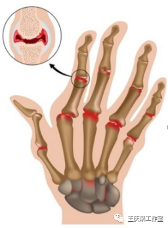

类风湿关节炎通常从较小的关节开始,此后会发展到较大的关节,晨僵通常在1小时以上,常常伴有关节的肿胀。发病通常是对称的。

另外类风湿性关节炎造成的关节变形,具有独特之处,如:手指天鹅颈样、钮扣花样畸形。而骨性关节炎则没有这种典型的表现。